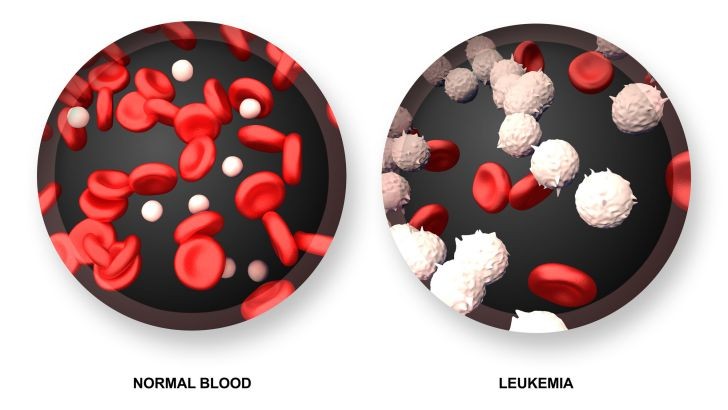

Which of these cells is affected by infection?

Platelets

White blood cells

Red blood cells

Plasma

What is the primary component of blood in terms of volume?

Platelets

Red blood cells

White blood cells

Water

What is leukemia?

A low white blood cell count

A low white blood cell count

A low platelet count

Cancer of blood cell producing tissue